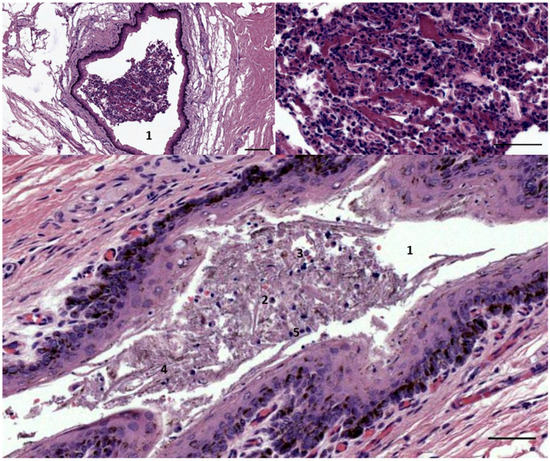

3.1. Ear Canal-Associated Lymphoid Tissue (ECALT)

3.2. Nodular Lymphoid Tissue

3.3. Immunoreactive Tissue